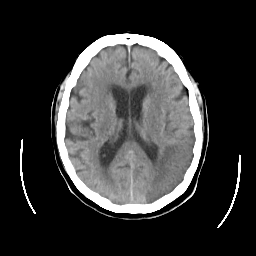

CT Study #2 -- Slice #16